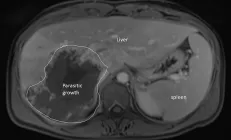

При этом около половины всех случаев рака печени можно легко предотвратить.

Избыток жира ухудшает работу белка HNF4, подавляющего рост опухоли.